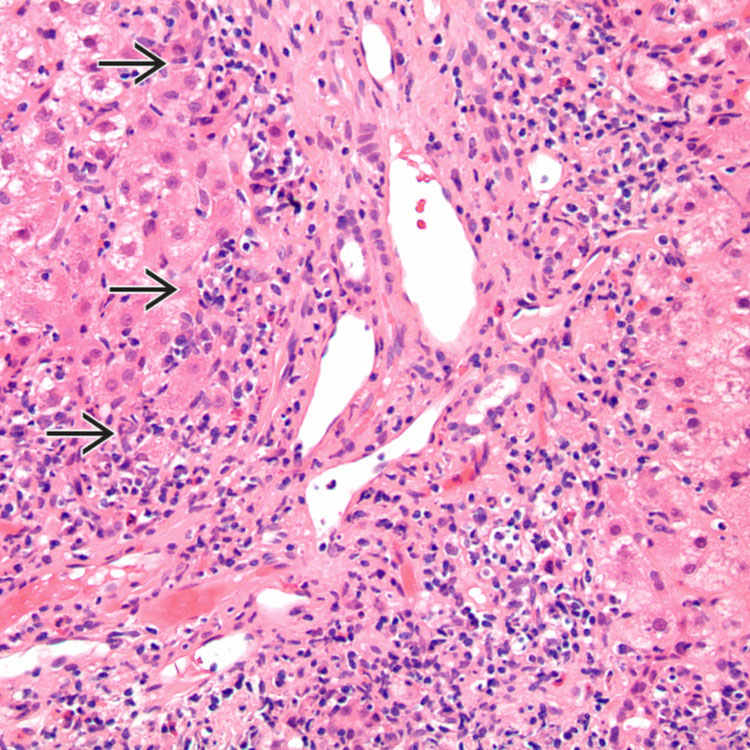

Histopathology of a 57yearold man with acuteonset autoimmune... Download Scientific Diagram Autoimmune Hepatitis Histopathology Simple system evaluating 4 laboratory and histological factors: Autoimmune hepatitis, histology, lobular hepatitis, portal hepatitis key points • autoimmune hepatitis (aih) is an autoimmune liver disease that may. This activity reviews the pathophysiology, causes, presentation, and diagnosis of autoimmune hepatitis and highlights the role of the interprofessional team in its management. The criteria proposed in this consensus statement provide a. Autoimmune Hepatitis Histopathology.

Autoimmune Hepatitis Photograph by Nigel Downer/science Photo Library Fine Art America